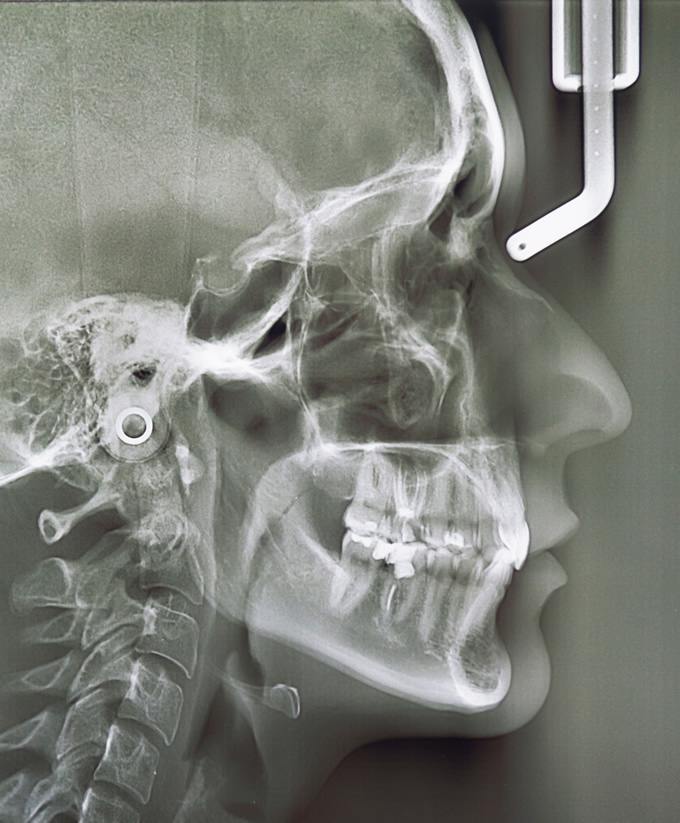

マウスピース矯正において、治療前の診査・診断が非常に大切になります。当医院では患者さまの口腔環境に応じて、顎関節の検査、噛み合わせ検査、顎の骨の大きさや位置関係、歯の角度などの分析を行うセファロ分析、最新の口腔内3Dスキャナーを導入し、矯正治療の事前シミュレーションなど様々な診査、分析を行います。

この診査・診断、分析は、豊富な経験と知識が必要になります。治療計画通りに歯が動くのか、表面的な審美性だけでなく、歯根部分の正常移動やかみ合わせはどうかなど、様々な角度から治療前に診査、診断を行います。